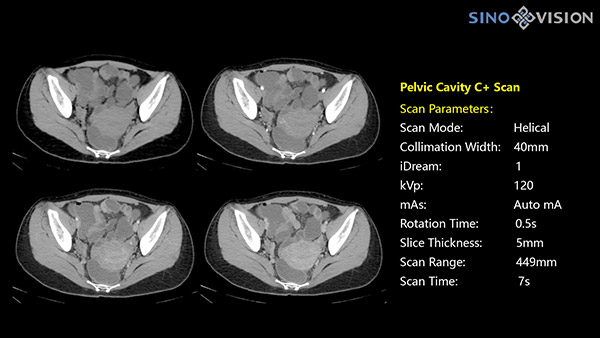

Инновационный 128-срезовый компьютерный томограф SinoVision InsitumCT 568 – это сочетание высокой скорости работы, низкой дозы и максимума возможностей для подавляющего большинства клинических случаев, как в рутинных, так и в углубленных специализированных исследованиях, в том числе педиатрические и кардиологические исследования при сверхнизких дозах.

Полнофункциональный 128-резовый компьютерный томограф InsitumCT 568 - это лучшее в новом поколении широкодиапазонных томографов с 128 срезами и большой диафрагмой. Этот КТ-сканер с большой апертурой обеспечивает 128 срезов КТ с диафрагмой 76 см, улучшает разрешение изображения до 21Lp/cm, помогает точно диагностировать и лечить заболевания, а также значительно улучшает клинические характеристики и расширяемость оборудования. Позволяет реализовать визуализацию в высоком разрешении и в малых дозах лучевой нагрузки.

Полнофункциональная платформа клинической диагностики может точно определять местонахождение и диагностировать общие повреждения качественно и количественно, а также достигать полнофункциональных клинических показателей, включая обширные кардиологические исследования со сверхнизкими дозами лучевой нагрузки.

Характеристики сканирования

- Минимальное время одного оборота рентгеновской трубки: От 0.48 до 2 сек